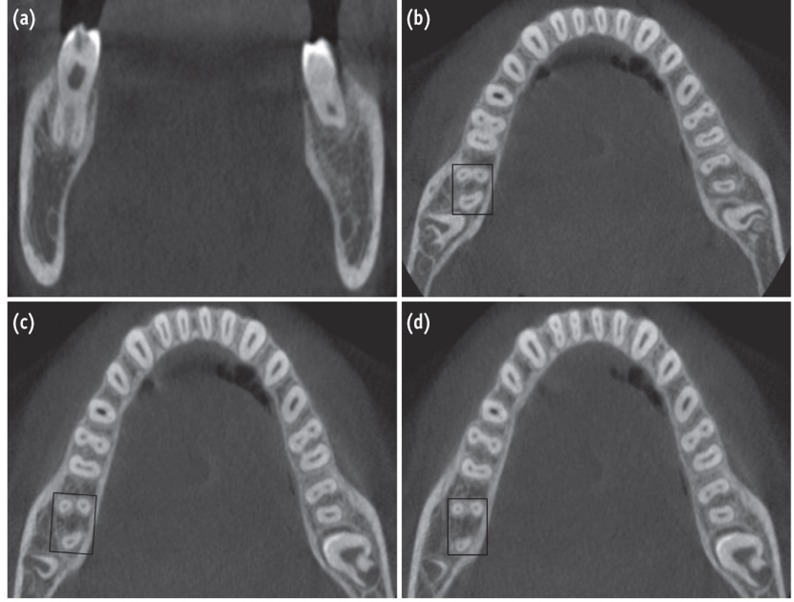

To confirm this rare and unusual morphology, dental imaging of the tooth with the help of CBCT (Carestream CS 9300, Carestream Dental LLC, Atlanta, GA, USA) was planned. An informed consent was obtained from the patient, and a multi-slice scans of the mandible was performed with a tube voltage of 90 kV and a tube current of 15 mA. All measures were taken to protect the patient from radiation. The involved tooth was focused, and the cross-sectional images were obtained in transverse, axial, and sagittal planes (Figures 3a - 3d). All images were analyzed with the help of CS 3D Imaging software (Carestream Dental LLC). Horizontal slices of the molar were obtained at 0.5-mm thickness, and were studied at different levels (coronal, middle, and apical third of the roots) to determine the level of root bifurcation and degree of root separation (Figures 3b - 3d). The images confirmed that the right mandibular second molar had 2 mesial roots and 1 distal root with independent canal in each. The mesial roots were well separated and were bifurcated at the level of coronal one third. In contrast, the contralateral mandibular second molar was asymmetrical. It had 2 roots, 1 mesial, and 1 distal with 2 canals in the mesial root and 1 canal in the distal root (Figures 3a - 3d).

Conventional intra-oral periapical radiographs has been the standard method for ascertaining varying morphology of the root and root canal system. If the outlines of the roots are unclear, the root canal shows sharp density changes or the apices cannot be well defined, then extra roots can be suspected.8 The use of a preoperative radiograph and an additional radiographic view from a 20-degree mesial or distal projection aids in the accurate detection of the periodontal ligament outlines, thus facilitating the interpretation of external root anatomy. Two periodontal ligament spaces on one side of a root and the periodontal ligament space crossing over roots are important observations that can indicate either the presence of 2 mesial roots, bifurcation of the mesial root, or a very broad faciolingually oriented mesial root.17 In our case, a 20-degree mesial angulation periapical radiograph of the right mandibular second molars revealed double periodontal ligament spaces in the mesial roots indicating the presence of an accessory mesial root (Figure 1a). CBCT investigations confirmed the existence 2 well separated mesial roots in which the level of bifurcation is at the coronal third (Figures 3a - 3d).

(a) Transverse section cone-beam computed tomography (CBCT) scan image of tooth #47 clearly showing two separate mesial roots. Axial section of CBCT scan image (b) at the coronal third; (c) at the middle third; (d) at the apical third.

Figure 3 (a) Transverse section cone-beam computed tomography (CBCT) scan image of tooth #47 clearly showing two separate mesial roots. Axial section of CBCT scan image (b) at the coronal third; (c) at the middle third; (d) at the apical third.